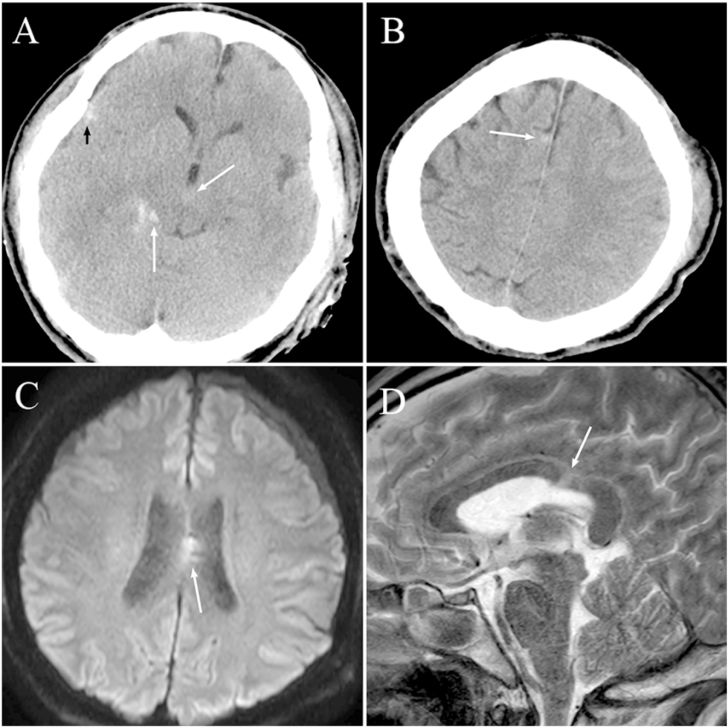

图1. 41岁男性患者,车祸伤。入院时GCS评分为7分。入院25分钟后行CT扫描提示中脑周围(A,白色箭头)、纵裂池(B,箭头)、右侧外侧裂(A,黑色箭头)以及侧裂谷(未标志)的tSAH,未见明显脑挫伤引起的脑实质血肿。10天后,MRI检查发现胼胝体非出血性DAI病变(C和D)。该患者出院时和6个月后预后差。